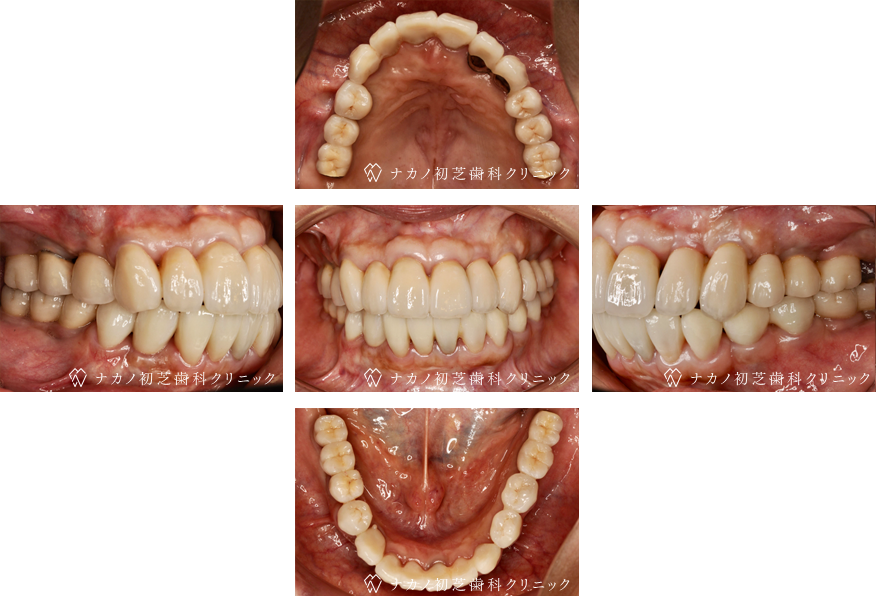

インプラント・13本 (60代女性)

-

BEFORE

AFTER

年齢 60代女性

治療内容 インプラント治療13本(骨造成の併用)

インプラント治療とは、歯を抜いた所にチタン製の人工歯根を埋入し、その上に歯を入れる方法です。骨を増やすことで、より審美的に治療が出来ました。費用 1本 400,000円(税込 440,000円)

リスク・副作用

腫れ・疼痛・違和感を感じるなどの症状を生じることがあります。